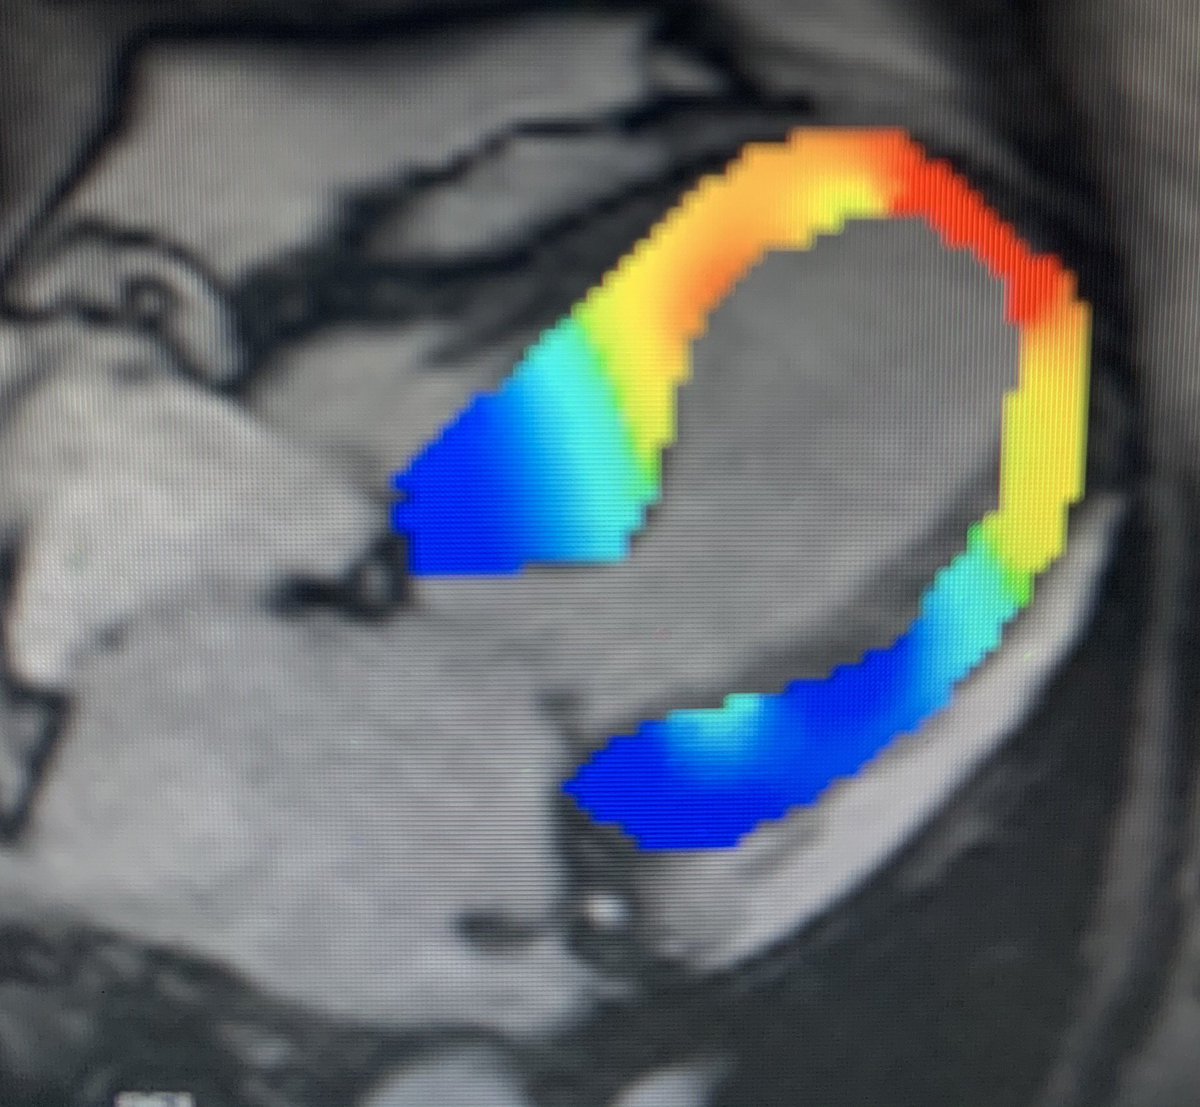

#whyCMR in TC: absence of LGE (at +5SD threshold) , but recent studies suggest LGE may be present

absence of LGE (at +5SD threshold) , but recent studies suggest LGE may be present  T1 and ECV mapping detect diffuse ECM abnormalities- here ECV normal at basal LV, increased at apical LV

T1 and ECV mapping detect diffuse ECM abnormalities- here ECV normal at basal LV, increased at apical LV strain can help detect myocardial deformation abnormalities

strain can help detect myocardial deformation abnormalities

absence of LGE (at +5SD threshold) , but recent studies suggest LGE may be present

absence of LGE (at +5SD threshold) , but recent studies suggest LGE may be present  T1 and ECV mapping detect diffuse ECM abnormalities- here ECV normal at basal LV, increased at apical LV

T1 and ECV mapping detect diffuse ECM abnormalities- here ECV normal at basal LV, increased at apical LV strain can help detect myocardial deformation abnormalities

strain can help detect myocardial deformation abnormalities